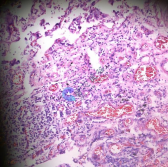

血管类器官HE染色 肺组织冰冻切片HE染色 |